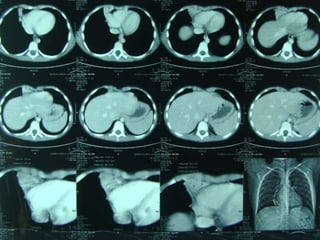

 LA TAC puede lograr

sospecha

 La Angio-TAC pulmonar

confirma al diagnóstico.

 Angiografía y el

Ecodoppler color, que

pueden mostrar la

irrigación sistémica del

secuestro.

OTRAS IMÁGENES  LATAC puede lograr sospecha  La Angio-TAC pulmonar confirma al diagnóstico.  Angiografía y el Ecodoppler color, que pueden mostrar la irrigación sistémica del secuestro.